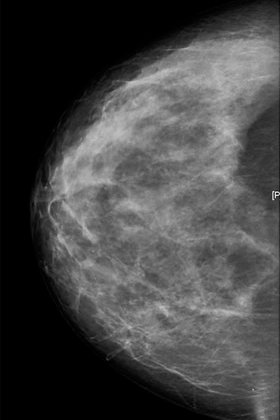

La mamografía es la técnica radiológica dedicada al estudio de la mama. Es el método de imagen básico e imprescindible en el diagnóstico de la patología mamaria, y el único reconocido como técnica de cribado para el cáncer de mama, permitiendo su detección precoz, y la única que ha demostrado una reducción de las tasas de mortalidad por cáncer de mama.

Es especialmente sensible en el diagnóstico de las microcalcificaciones, que pueden constituir un signo precoz del cáncer de mama, y son difícilmente o no detectables por otras técnicas de imagen (ecografía, resonancia magnética).

Visión de una mamografía